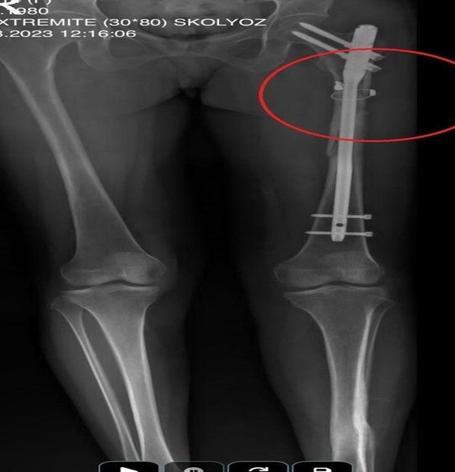

İlyas Sarıkaya, sevgilisi Fatma O.'yu da 8 kurşunla vurup, yaraladı. Arkadaşı Özaslan'ın cesedini önce çarşafa sonra da streç filme sarıp bantlayan Sarıkaya, eczaneden aldığı sargı bezi ve ilaçlarla pansumanını yaptığı sevgilisine yaralı haldeyken 21 gün boyunca cinsel saldırıda bulundu.

Fatma O., annesine yazdığı mesajda, "Odada ceset var. Telefon dinleniyor. Bana 8 el ateş etti. Yaralıyım. Polisi görürse önce beni öldürecek. Onu parayla kandırıp, evden çıkartın. Sonra da beni alın' dedi. Fatma O.’nun annesi, bu mesaj sonrası polise gidip şikayette bulundu. Polis, Fatma O.'nun annesi aracılığıyla Sarıkaya ile iletişime geçti. Fatma O.'nun annesi, telefonla aradığı Sarıkaya'yı, kızına para götürmesi için evine çağırdı. Ekipler, parayı almaya gelen Sarıkaya'yı kendilerine silah çekmesine rağmen yakaladi. Eve giden ekipler, ağır yaralı haldeki Fatma O. ve kokmaya başlayan cesetle karşılaştı.